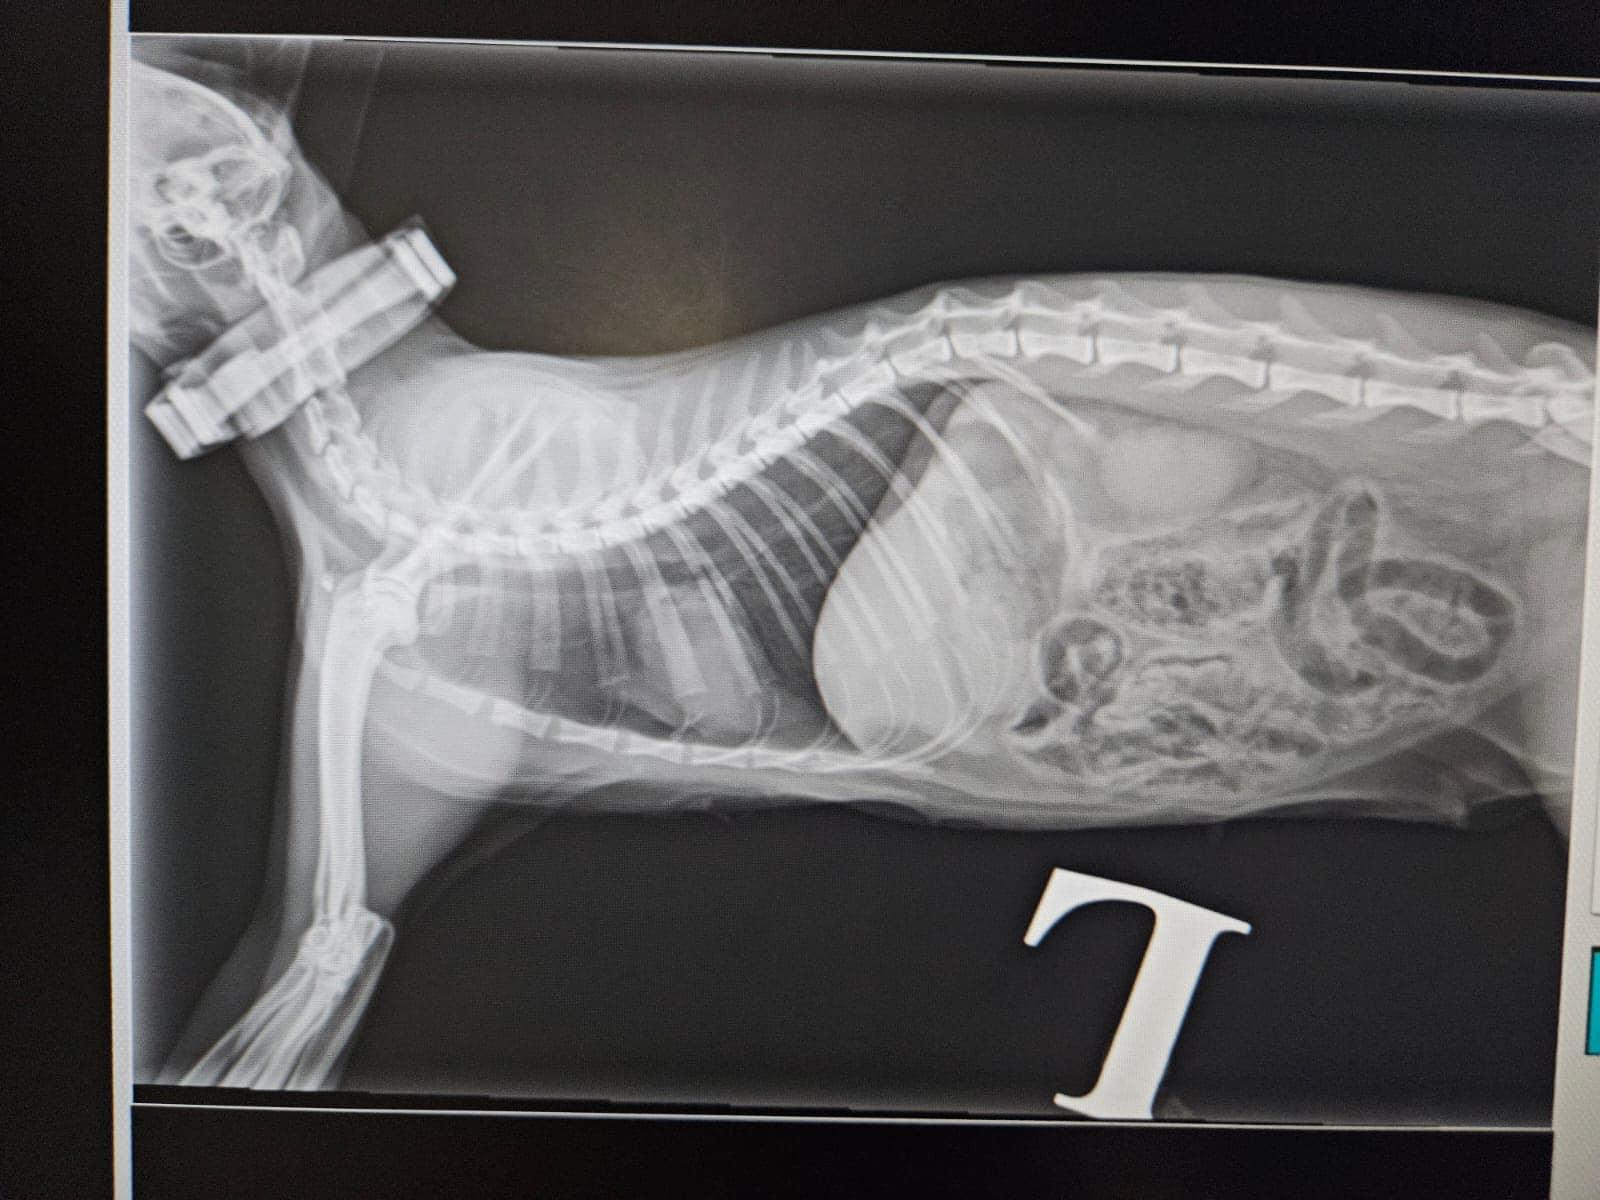

社交平台Facebook專頁「毛守救援」凌晨表示,昨晚錦田公路石崗菜站,有一隻雌性唐貓懷疑被白色私家車撞到,涉事司機不顧而去,捱撞唐貓重創倒臥路中,口鼻吐血,大腿位置有傷口,情況嚴重,有熱心司機見狀通知「毛守救援」,將受傷貓隻事後被送往動物診所接受搶救。

毛守救援上載多張照片和多條影片,可見唐貓倒在馬路,附近遺下血跡,一把女聲表示「撐住呀貓貓」。毛守救援指出,受傷唐貓已經接受絕育和剪耳,頸部戴上蝨帶,估計有主人,呼籲如有街坊認識受傷貓咪主人, 請致電6999 4221。